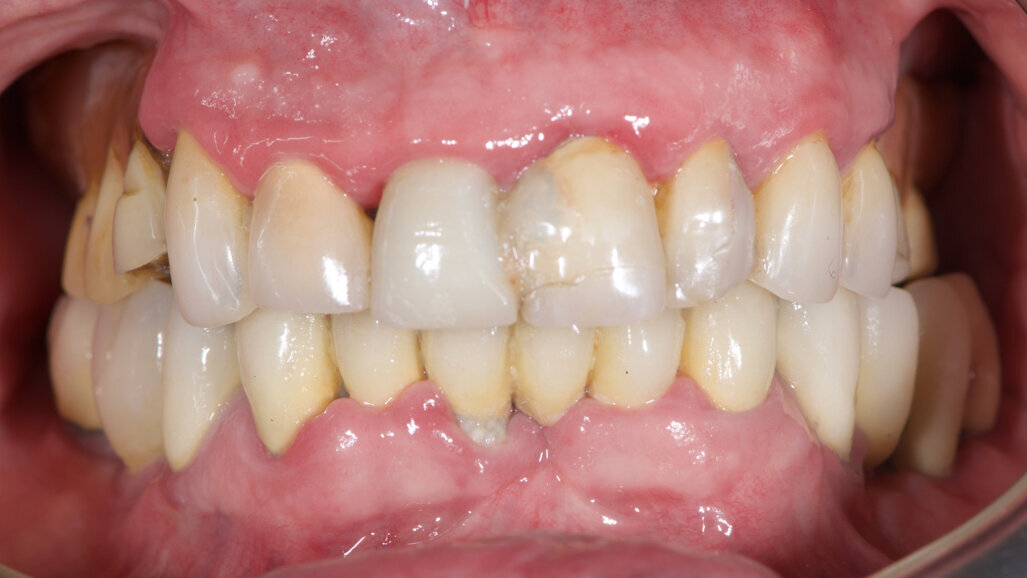

Fig. 2: Initial situation, occlusal view.

An 85-year-old partially edentulous patient was referred to our clinic for full-arch rehabilitation of the maxilla. The patient was in good general health and a non-smoker. His primary complaints included difficulty in chewing, maxillary pain and occasional halitosis. Clinical and radiographic evaluation revealed a short-span fixed metal–ceramic prosthesis supported by seven anterior maxillary teeth. The prosthesis had debonded, and four of the abutment teeth were structurally compromised. The remaining three showed varying degrees of caries and periodontal problems. A diagnosis of failing dentition was established (Figs. 1 & 2).

At the initial visit, digital impressions were captured using the Medit i700 scanner to document the residual teeth, soft tissue, existing prosthesis and opposing arch. The occlusal records were obtained at the current vertical dimension of occlusion and in centric relation. Mandibular movements were recorded with the zebris JMA jaw registration system (zebris Medical). Intra- and extra-oral photographs were also taken. A virtual diagnostic wax-up and a digital smile simulation were created based on these records (Smile Creator, exocad). Finally, eight implants were planned (Figs. 3 & 4) according to the new wax-up (exoplan 3.1, exocad), and both a surgical guide and a metal-reinforced temporary prosthesis were fabricated in advance (Figs. 5–7).